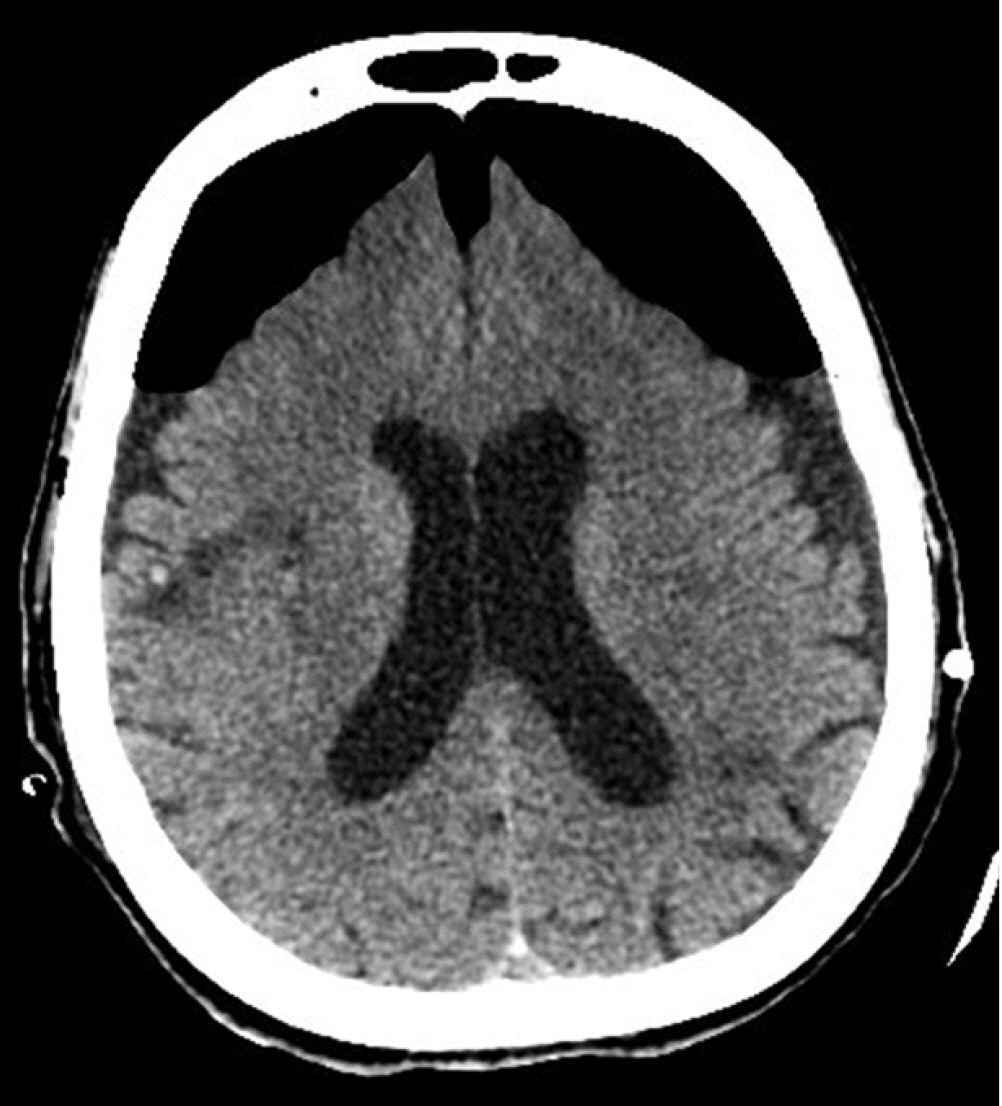

Our patient was an 84-year-old female with a past medical history of diabetes mellitus, hypertension, paroxysmal atrial fibrillation, and an old cerebrovascular event (left middle cerebral artery infarction) with no residual weakness. She was ambulatory with acceptable cardiorespiratory status for her age. Following a fall, she was admitted to our hospital with a left intertrochanteric femur fracture. On the next day, an orthopedic surgeon performed Gama nailing of the femur. The postoperative course was uneventful. On the 7th postoperative day; however, she developed right-sided hemiparesis and altered mental status. The Glasgow coma scale (GCS) was 10/15 (E4, V1, M5). Noncontrast computed tomography (NCCT) of the brain suggested bilateral cerebrospinal fluid (CSF) hygroma more strongly affecting the left side than the right side at the cerebral convexity (Figure 1). She was referred to a neurosurgeon and subsequently underwent a left parietal Burr hole and evacuation of CSF hygroma under general anesthesia. She was extubated in the postoperative period and remained in an intensive care unit (ICU) for neuro observation. Postoperatively, her GCS was 15/15 (E4, V5, M6), but she had persistent right-sided hemiparesis, which was similar to her preoperative state. Six hours postoperatively, she developed generalized tonic-clonic seizures, and her GCS dropped to 5/15 (E1, V1, M3). She underwent immediate intubation to secure her airway. She was sedated with a continuous infusion of fentanyl and midazolam, and she was connected to mechanical ventilation. She also received antiepileptic levetiracetam. Another NCCT of the brain revealed near-complete evacuation of the bilateral CSF hygroma and development of the classic “Mount Fuji” sign, indicating the formation of TPC (Figure 2). Her management included maintenance in a flat position in bed, 100% oxygen, sedation, an antiepileptic, and other brain-protective measures. She underwent immediately surgery, and a neurosurgeon performed left frontoparietal decompressive craniectomy under general anesthesia. Postoperatively, she was kept in the ICU under sedation. On the second postoperative day, a repeat NCCT of the brain showed near-complete resolution of the pneumocephalus. Her sedation was stopped, but her GCS did not improve beyond 9/15 (E4, V1, M4). On the 7th postoperative day, she underwent a tracheotomy for low GCS. Unfortunately, the patient developed other complications associated with her critical illness: ventilator-associated pneumonia, sepsis, acute kidney injury, and multi-organ failure. Finally, she succumbed to death on the 25th postoperative day. Because the patient was deceased, we obtained consent from her son for publication of this case report. This case report was approved by the head of the ICU of our hospital.

Pneumocephalus can be investigated by plain X-ray of the skull and computed tomography (CT) of the brain [5]. Although X-ray of the skull can detect a large pneumocephalus, it is seldom used with the advancement of CT; CT of the brain is the investigation of choice [9]. When pneumocephalus is detected on brain CT, the patient should be investigated for a skull base fracture or CSF leak [1]. Radiological signs described for diagnosis of pneumocephalus/TPC are the peaking sign, Mount Fuji sign, and air bubble sign [5,9]. The peaking sign is bilateral compression of the frontal lobes caused by trapped air in the subdural space. This sign demonstrates no separation of the frontal lobes and is more common in pneumocephalus than in TPC [5,9]. The Mount Fuji sign is bilateral compression and separation of the frontal lobes due to trapped subdural and interhemispheric space air. It is observed as non-attenuating collections formed between the two frontal lobes and is specific to TPC [5,9]. The air bubble sign is the presence of multiple air bubbles scattered around the cisterns. It is caused mainly by a tear in the arachnoid membrane and is more common in TPC [5,9].